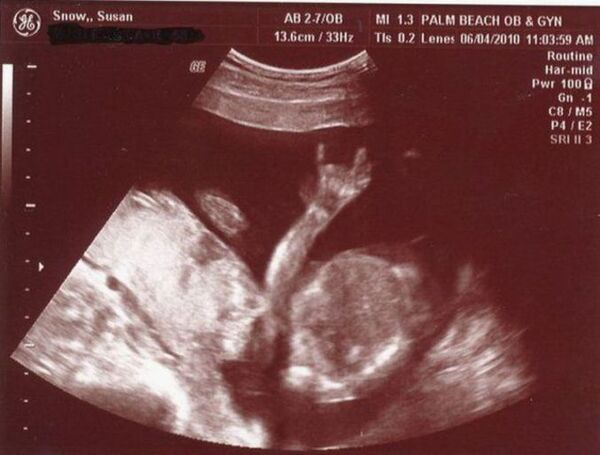

Bebekler anne karnında ne yapar?